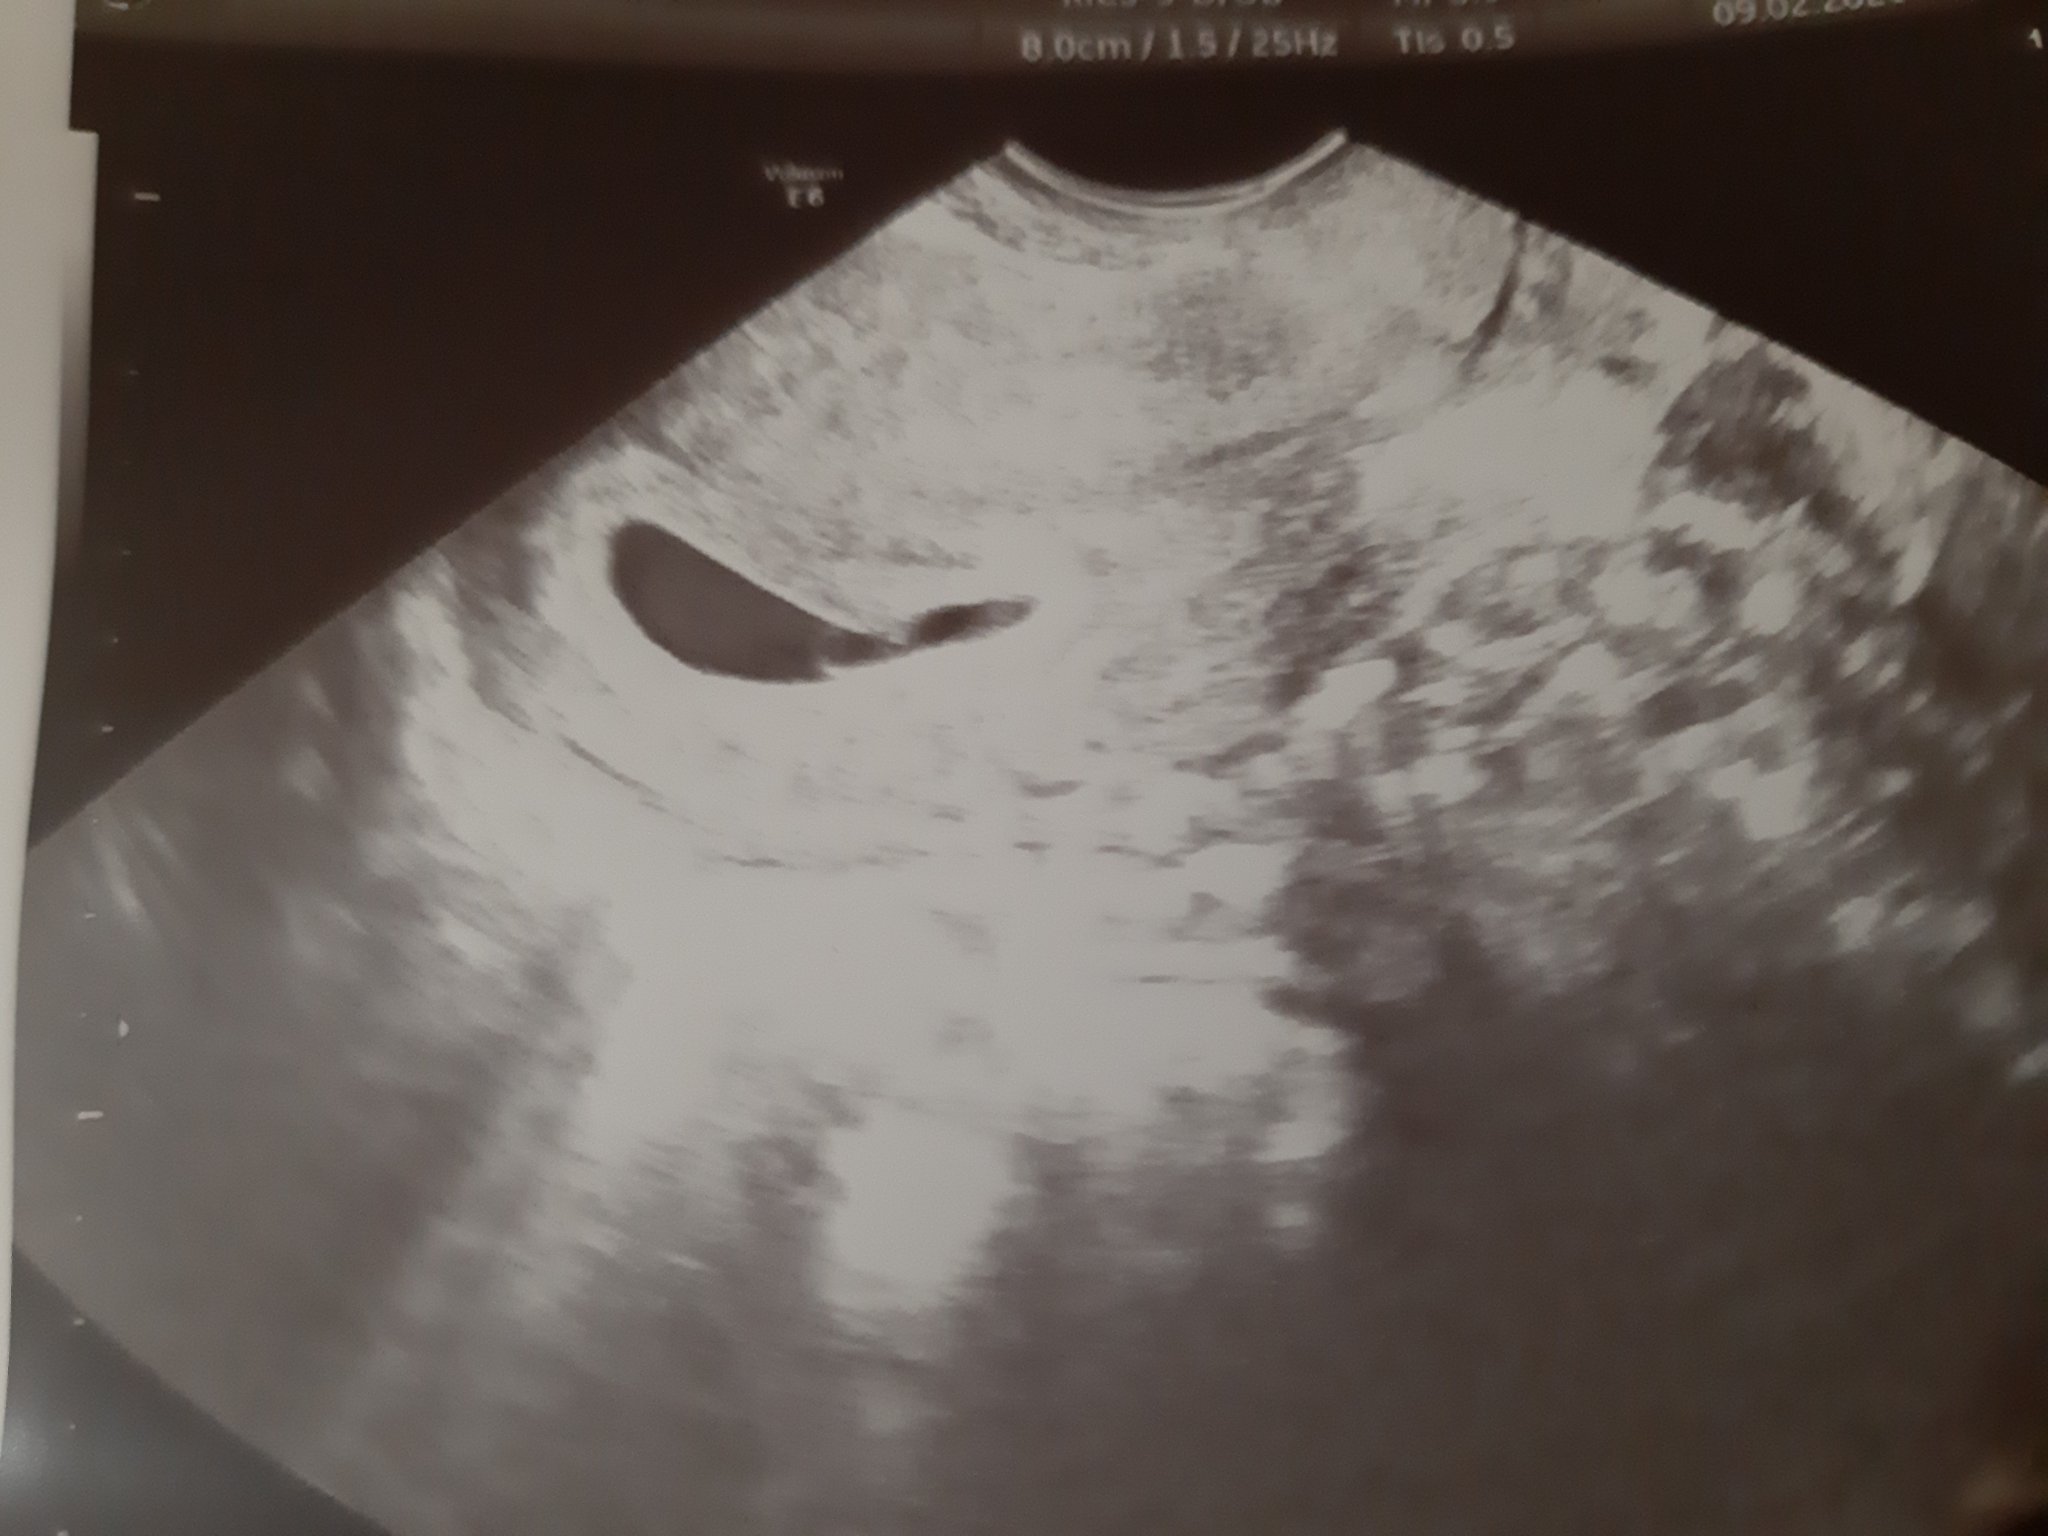

Бях на преглед, чухме сърчице

след всички премеждия и изпитания, които минахме това беше най-прекрасният звук!

в 6 г.с. съм, според календара термина ми е на 03/10.